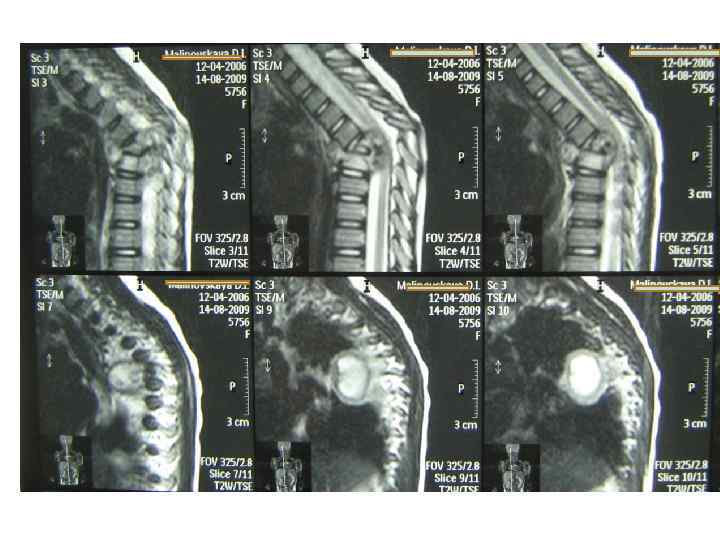

МРТ (моделирование)

Последствия туберкулезного спондилита, перенесенного в детстве (МРТ)